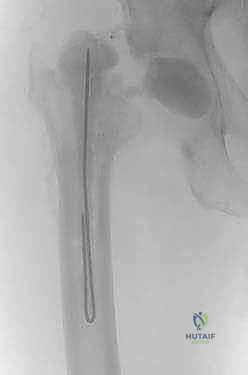

الفترة الانتقالية: ما بين المرحلتين (6 إلى 12 أسبوعاً)

بمجرد انتهاء المرحلة الأولى، يدخل المريض في مرحلة التعافي والمراقبة الدقيقة.

- المضادات الحيوية الوريدية: بالإضافة إلى المضاد الموضعي من الفاصل، يتلقى المريض مضادات حيوية عبر الوريد (غالباً عبر قسطرة وريدية مركزية PICC line) لمدة 4 إلى 6 أسابيع، بناءً على توصيات طبيب الأمراض المعدية.

- الحركة: يُسمح للمريض بالحركة باستخدام المشاية أو العكازات. إذا كان الفاصل من النوع المفصلي، يمكنه وضع وزن جزئي على القدم.

- المراقبة المخبرية: يتم فحص مستويات (ESR) و (CRP) أسبوعياً. الهدف هو رؤية انخفاض تدريجي ومستمر في هذه المؤشرات حتى تصل إلى المستويات الطبيعية، مما يدل على القضاء على العدوى.